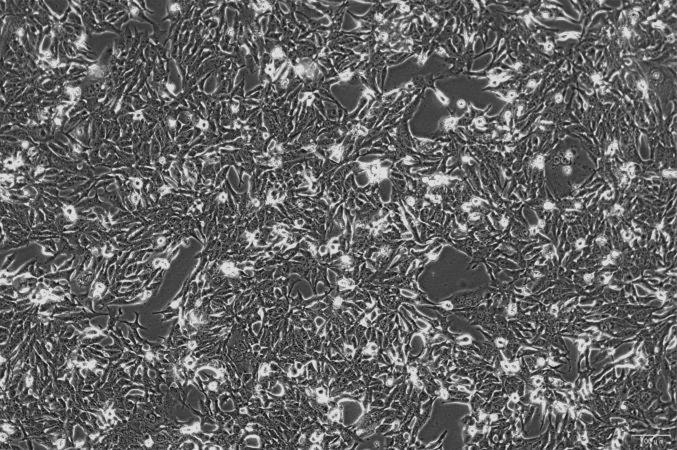

OriCell®NCI-H1703 人肺鳞癌细胞系

人肺鳞癌细胞系(NCI-H1703)于 1987 年建系,来源自一位 54 岁患有非小细胞肺癌的白人男性,该患者为吸烟者。

贴壁生长;上皮细胞样 |